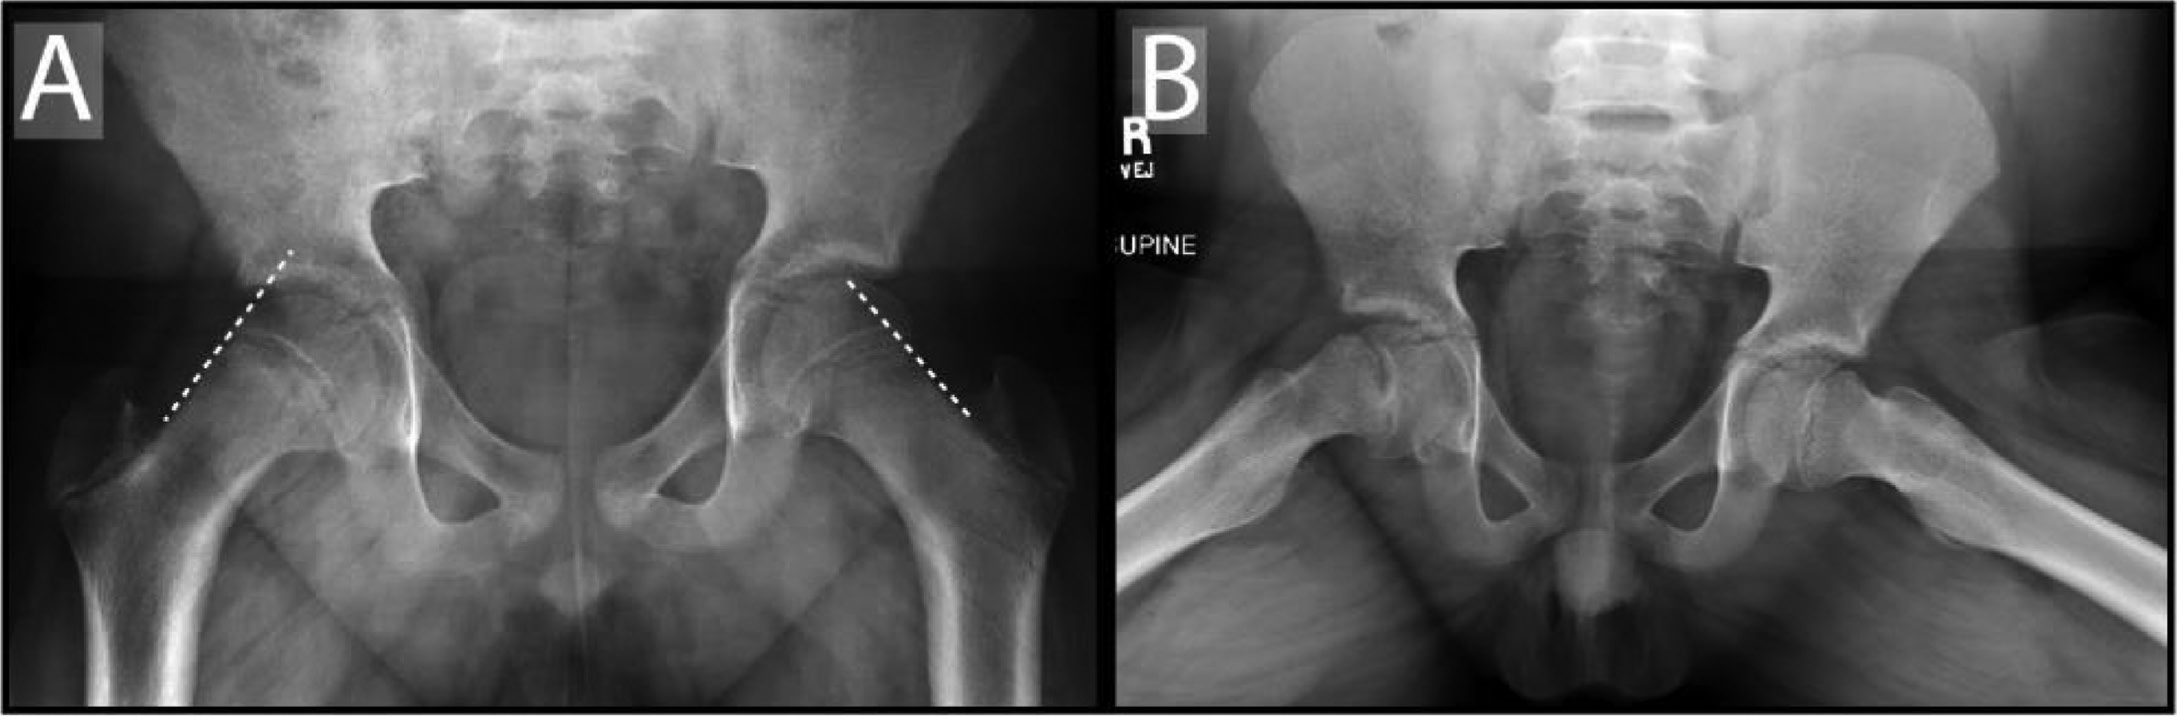

In situ fixation is the gold standard for the treatment of stable SCFE. Current standards for in situ pinning (ISP) of a stable SCFE include the placement of one cannulated screw placed perpendicular to the physis, penetrating the epiphysis at the center with at least four screw threads crossing the physis (Figure 4).

Figure 4. Bilateral in situ screw fixation of stable slipped capital femoral epiphysis. Note the central position of the screw on the AP and lateral views with at least four screw threads in the epiphysis.

jposna2022589_fig4.jpg

Additionally, to prevent penetration into the joint space, the findings from Senthi et al.43 recommend a distance of at least 5 mm from the subchondral bone on all views. ISP effectively makes no overt attempt to correct the presenting deformity but focuses on preventing additional slip and subsequent deformity instead. A serendipitous reduction may be achieved during patient positioning with internal rotation of the hip to position the patella directly up. Napora et al.44 acknowledged that this serendipitous reduction can be performed purposefully without increased rates of AVN in unstable SCFE. However, forceful reduction is not performed to avoid iatrogenic displacement that may injure the retinacular vessels supplying the epiphysis.

Similarly, the gold standard for management of unstable SCFE remains ISP. In contrast to stable SCFE, unstable SCFE is generally treated in an urgent fashion similar to a transphyseal femoral neck fracture. Treatment is also unique from management of stable SCFE with the addition of 1) placement of two screws rather than a single screw, 2) the addition of capsulotomy to address possible intracapsular hematoma, and 3) monitoring of capital femoral epiphyseal perfusion.